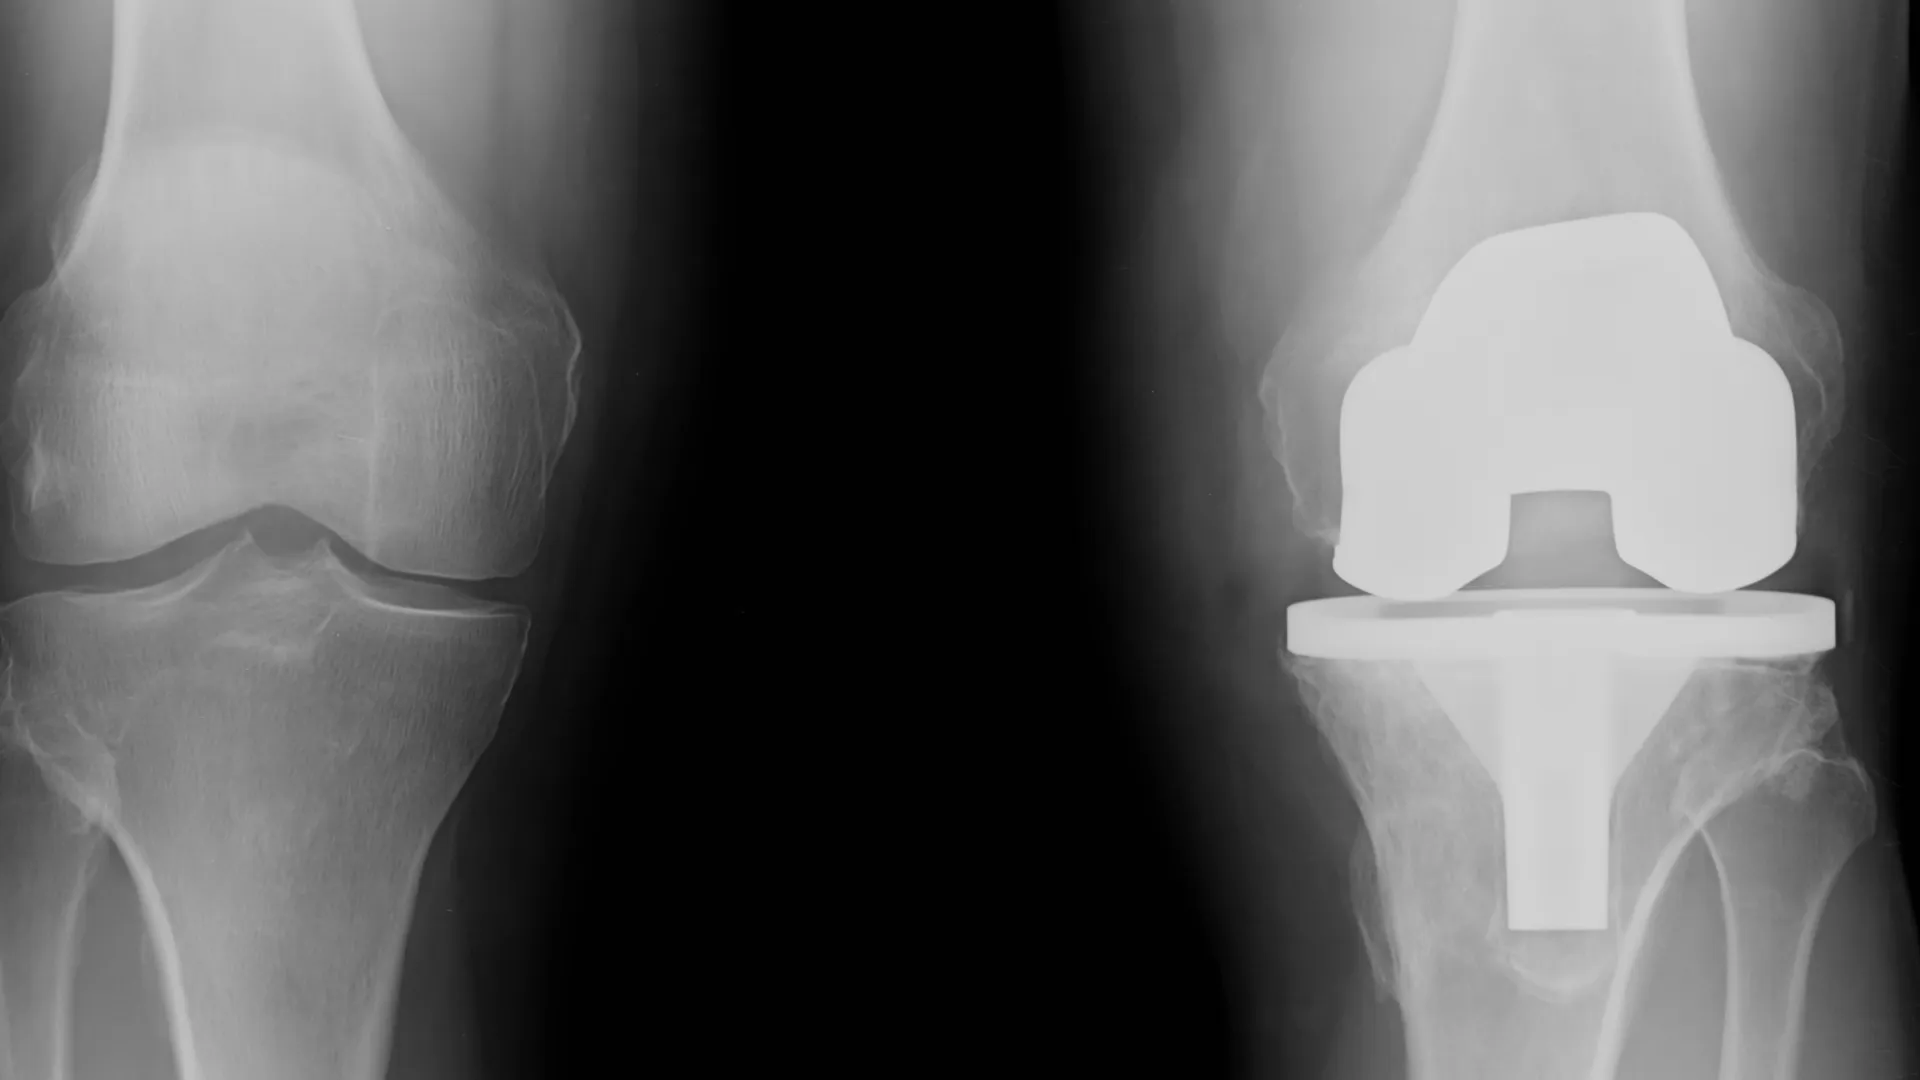

La Unidad de Recambio de Prótesis de la Fundación Hospitalarias Madrid está superespecializada en cirugía reconstructiva de cadera y rodilla, con especial dedicación a los casos más complejos: revisiones, prótesis infectadas, fracasadas, dolorosas, inestables, aflojadas o con pérdida ósea que comprometa la función de la extremidad.

- Prótesis de cadera y rodilla dolorosas, inestables, infectadas, aflojadas o con pérdida ósea.

- Prótesis primarias de cadera y rodilla.